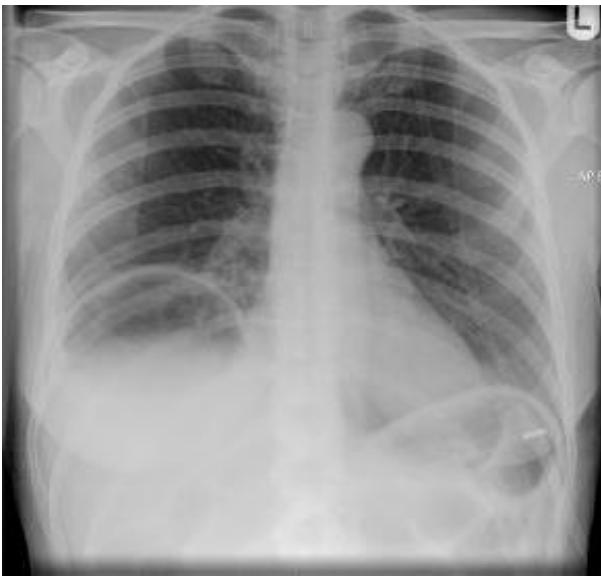

- Diagnosis: Right-sided Pneumothorax.

- Tension Pneumothorax (Clinical Diagnosis):

- Tracheal deviation to the opposite side.

- Hyperresonance on percussion.

- Congested neck veins, hemodynamic instability.

- Treatment of Tension Pneumothorax: Urgent needle decompression followed by chest tube insertion.